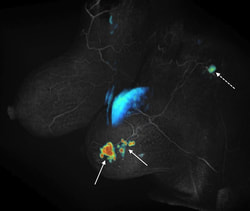

Fast dynamic MRI

Fast dynamic MRISpatial and temporal resolution are competing requirements in dynamic MRI, often requiring compromises. We are  developing methods based on view sharing,  compressed sensing and combinations of the two along with novel acquisition schemes to accelerate dynamic contrast enhanced imaging. The main applications are in cancer imaging (breast, prostate, liver) as well as quantification of renal function. One such method called Differential Subsampling with Cartesian Ordering or DISCO is now a product on GE MRI scanners. The picture on the left shows initial slope of contrast enhancement wash-in overlaid on a DISCO post contrast image obtained from a patient with invasive ductal carcinoma (solid arrows) with a likely metastatic axillary node (dotted arrow).